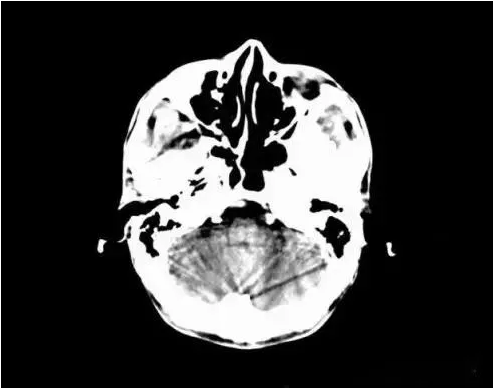

6、部分容積效應(yīng)產(chǎn)生的偽影及對策

部分容積效應(yīng)偽影的形狀可因物體的不同而不一樣,一般在重建后橫斷面圖像上可見條形、環(huán)形或大片干擾的偽像。最常見和典型的現(xiàn)象是在頭顱橫斷面時的顳部出現(xiàn)的條狀偽影,又稱哼氏偽影。該偽影現(xiàn)象可采用薄層掃描而減弱;在西門子系列的CT機中.用VAR掃描技術(shù)可抑制該偽影。